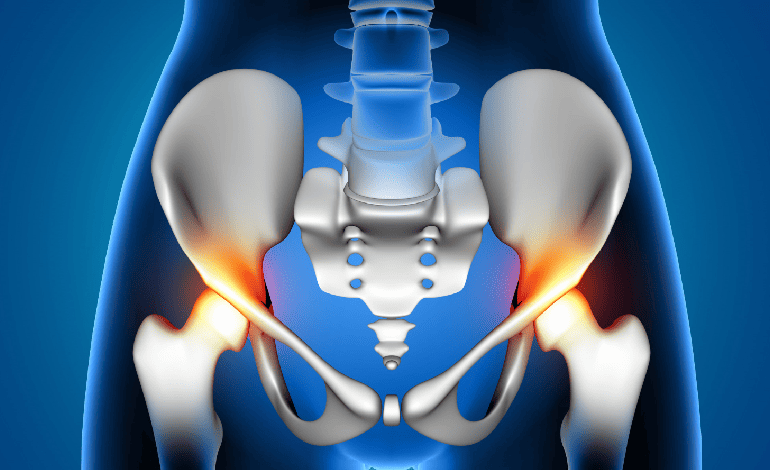

Procedimiento de Remplazo total de cadera en Cuernavaca e Iguala para Traumatología Y Ortopedia

El Remplazo total de cadera en Cuernavaca e Iguala es un procedimiento de vanguardia en Traumatología Y Ortopedia. Este procedimiento, que integra Valoración de primera vez y subsecuente, ofrece soluciones innovadoras para restaurar la movilidad y aliviar el dolor.

El Remplazo total de cadera en Cuernavaca e Iguala proporciona múltiples beneficios en el ámbito de Traumatología Y Ortopedia, incluyendo la mejora de la función articular y la reducción del dolor. Además, este procedimiento integra Valoración de primera vez y subsecuente para potenciar los resultados terapéuticos.

Mediante el uso de técnicas quirúrgicas avanzadas, el Remplazo total de cadera en Cuernavaca e Iguala se realiza en un entorno seguro y controlado en Traumatología Y Ortopedia. Este procedimiento se complementa con Valoración de primera vez y subsecuente, asegurando una intervención precisa y eficaz.

El proceso del Remplazo total de cadera en Cuernavaca e Iguala incluye una evaluación detallada y un plan quirúrgico personalizado en Traumatología Y Ortopedia. Durante la intervención se emplean técnicas complementarias como Valoración de primera vez y subsecuente para optimizar la recuperación.

La rehabilitación tras el Remplazo total de cadera en Cuernavaca e Iguala se planifica cuidadosamente en el marco de Traumatología Y Ortopedia. El proceso de recuperación se ve fortalecido al integrar Valoración de primera vez y subsecuente, lo que permite a los pacientes retomar sus actividades diarias con mayor rapidez y seguridad.

Los resultados del Remplazo total de cadera en Cuernavaca e Iguala se reflejan en una mejora significativa de la calidad de vida en el área de Traumatología Y Ortopedia. Gracias a la incorporación de Valoración de primera vez y subsecuente, los pacientes experimentan una restauración completa de la funcionalidad y alivio prolongado del dolor.